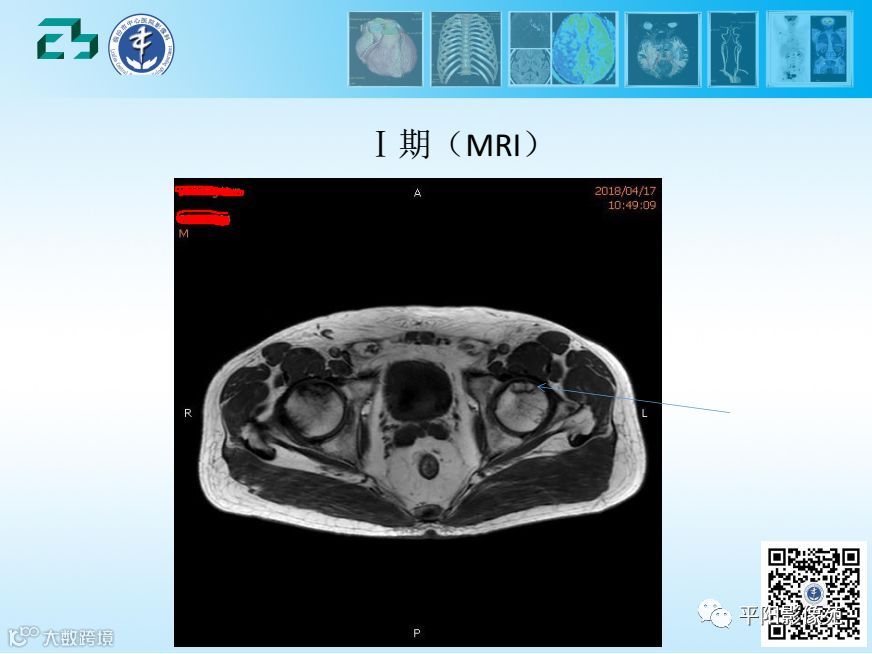

【影像基础】股骨头缺血坏死分期